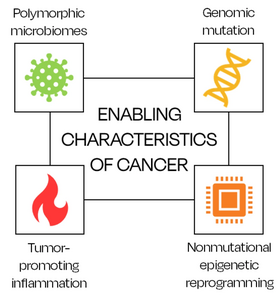

Pour que les cellules cancéreuses acquièrent les dix caractéristiques, quatre conditions semblent nécessaires : une mutation génomique, une reprogrammation épigénétique non mutationnelle, un contexte inflammatoire favorisant les tumeurs et une perturbation des microbiotes[18].

L’état inflammatoire est également vital pour favoriser la progression tumorale. Même si le système immunitaire a toujours été considéré comme un outil de protection du corps humain, des études ont démontré comment l'inflammation fournit des molécules bioactives au microenvironnement tumoral, qui sont vitales pour permettre la progression du cancer[18],[51],[36]. Un lien significatif avec l’inflammation est donné par le rôle des microbiotes. Les microbiomes polymorphes – notamment ceux de l’intestin, des poumons, de la cavité buccale, du vagin/col de l’utérus et de la peau – sont tous connus pour avoir un impact sur la croissance tumorale, la capacité d’évasion immunitaire, l’instabilité génomique et la résistance thérapeutique[37],[52]. Le microbiome intestinal est extrêmement important pour le bien-être humain et il a déjà été prouvé qu’il influence l’incidence et la pathogenèse du cancer du côlon[53].